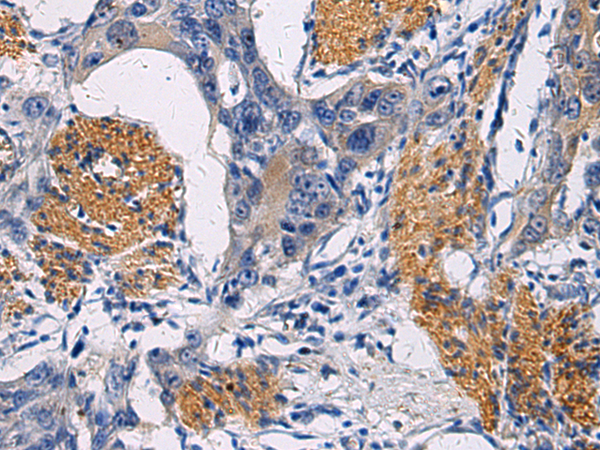

IHC positive control: |

Human esophagus cancer |